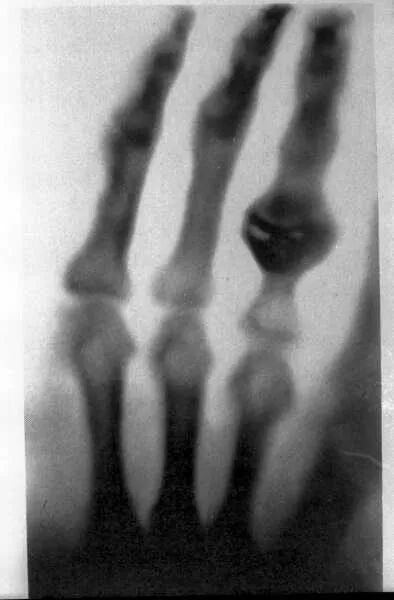

经过伦琴大哥对实验装置的优化改良,1895年12月22,伦琴请夫人来实验室,用他夫人的手拍下了第一张人手 X 射线照片,他夫人手指上戴着他们结婚的戒指。

(李鸿章是拍X光片检查枪伤的第一个中国人)。